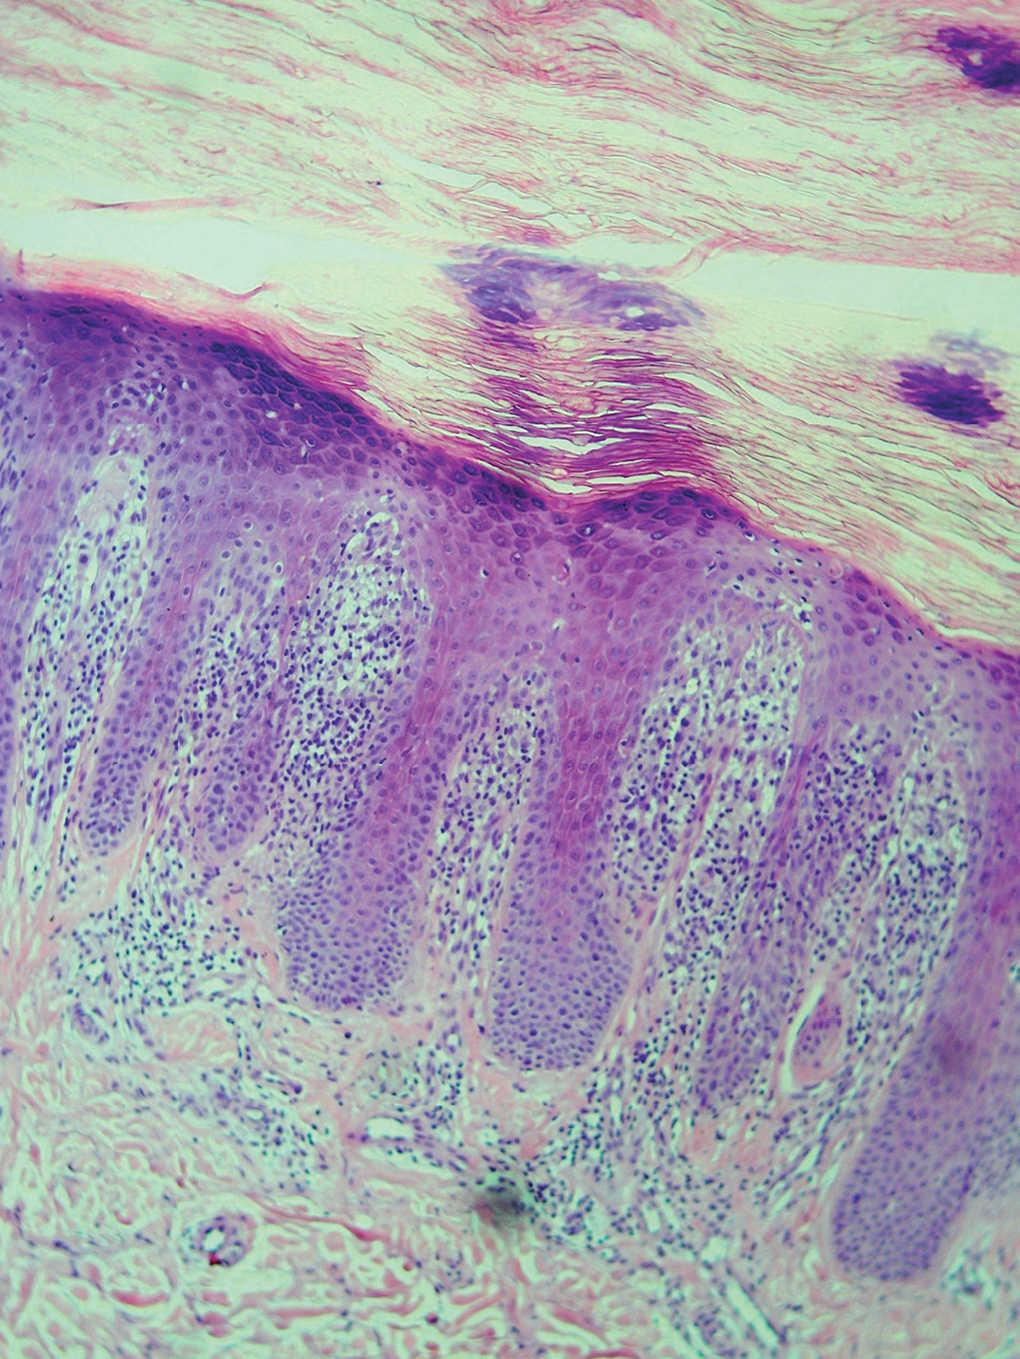

En la exploración física se observaba de forma bilateral y simétrica en las caras laterales (de predominio radial) y en la cara palmar de los primeros 3 dedos de ambas manos y salpicando de forma aislada las palmas de las manos, lesiones hiperqueratósicas, escamosas, hiperpigmentadas, con alguna zona fisurada, que recordaban callosidades (figs. 1 y 2). La afectación de la mano derecha era más intensa. El paciente no presentaba lesiones cutáneas en otras localizaciones. Las pruebas epicutáneas resultaron positivas (+ +) para la mezcla de mercaptos. Se prescribió un corticoide tópico, se insistió en la utilización de cremas emolientes y se le proporcionó una hoja informativa del alérgeno positivo. En las revisiones posteriores a los 4 y 8 meses el paciente apenas presentaba mejoría a pesar de haber seguido los consejos indicados. En ese momento no realizaba ningún trabajo manual, ni refería tener contacto actual con el alérgeno positivo (mezcla de mercaptos). Se realizó una biopsia de las lesiones cutáneas, que mostró una epidermis con hiperqueratosis y acantosis irregular, con zonas de degeneración vacuolar, cuerpos coloides y focos de exocitosis linfocitaria. En toda la dermis superficial se observó un infiltrado inflamatorio linfocitario denso dispuesto de forma paralela a la epidermis (fig. 3).

Fig. 3.--Epidermis: con acantosis irregular y zonas de degeneración vacuolar, cuerpos coloides y exocitosis escasa de linfocitos. Dermis con infiltrado denso linfocitario en la dermis superficial. (Hematoxilina-eosina, x10.)

Los pacientes con ACAS presentan un cuadro clínico bastante homogéneo que se ha denominado «síndrome antisintetasa» caracterizado por la combinación completa o incompleta de los siguientes signos: miositis, enfermedad pulmonar intersticial, artralgias o artritis, fiebre, lesiones hiperqueratósicas en las manos («manos de mecánico») y fenómeno de Raynaud 1-3. Esta variabilidad en la presentación clínica del síndrome ya ha sido referida por distintos autores 11, y es difícil que se observen todos los signos en un mismo paciente. La afectación cutánea característica de este síndrome son las denominadas «manos de mecánico», que aparece en el 70 % de los casos 10 y que consiste en hiperqueratosis, hiperpigmentación y fisuración de la piel de las caras laterales, sobre todo la cara radial y en la cara palmar de los dedos de ambas manos, afectando también a la palma. Las lesiones de «manos de mecánico» fueron descritas por primera vez por Stahl et al 12 como lesiones cutáneas asociadas a procesos de diferente índole que cursaban con miositis. Otros casos descritos con posterioridad confirmaron esta idea 13-15. Recuerdan a una dermatitis irritativa de las manos por una actividad laboral intensa. Son lesiones apenas pruriginosas. Histológicamente se caracterizan por una epidermis hiperqueratósica con algún foco de paraqueratosis y acantosis irregular con zonas de degeneración vacuolar, cuerpos coloides y focos de exocitosis de linfocitos hacia epidermis. En la dermis existe un infiltrado linfocitario denso paralelo a la epidermis.